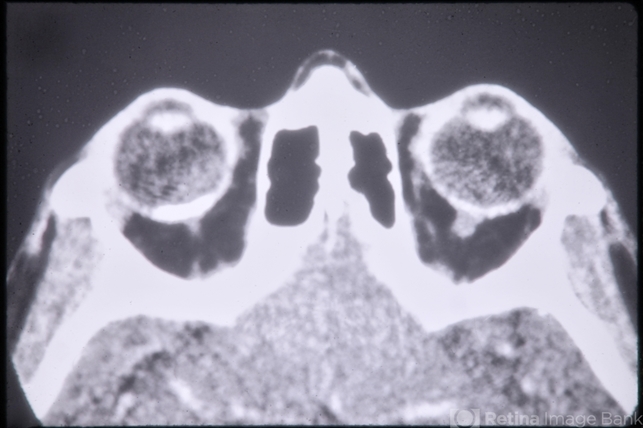

CT Scan of Brain Showing Cerebral Hypoplasia

Linear Nevus Sebaceous Syndrome

CT scan, cerebral hypoplasia, linear nevus sebaceous syndrome